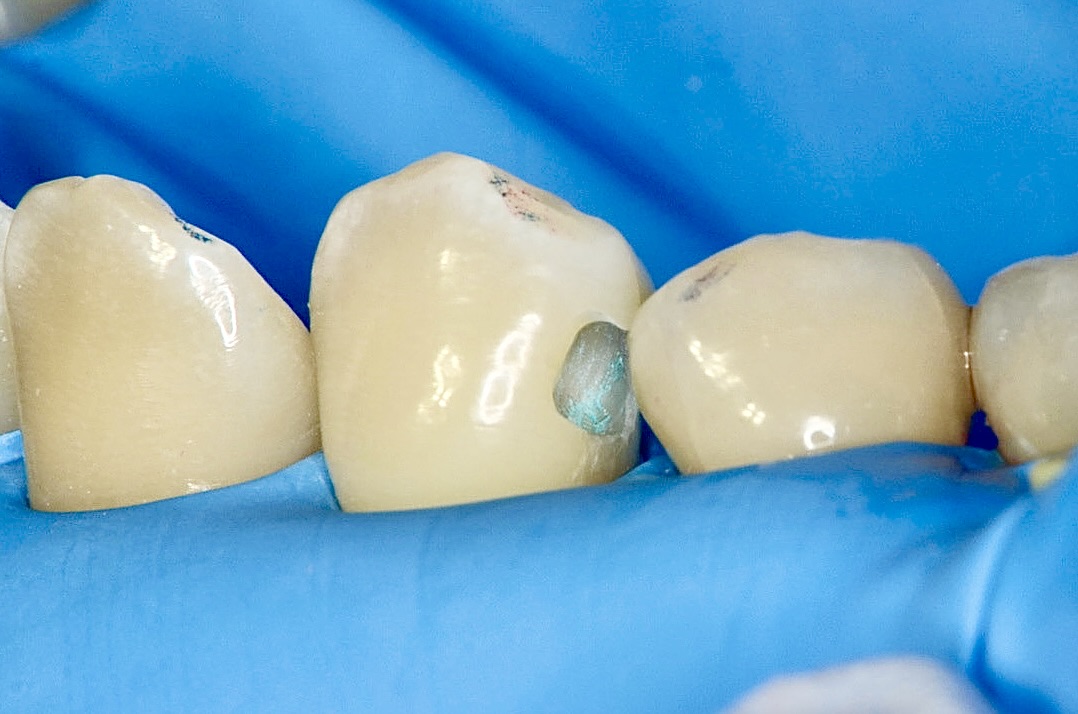

ホリゾンタルスロット

3番の健康な歯の部分を削る量をできるだけ少なくしたいので、歯の横からトンネルのように削っていきます。 -

青い齲蝕検知液で虫歯を染める

齲蝕検知液で染めると虫歯が歯の中で広がっているのがわかります。 -